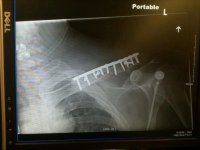

Me and my family Dr. were out in the Freemont area going from the Husky Monument over to inscription canyon. He fell and broke his collarbone. Had to ride his bike the 25+ miles back to the truck. On the way home he's making phone calls. We get home at 5:00, he's getting wheeled into the OR at 8:00 and in recovery at 1:00am. 17 screws and a plate later....